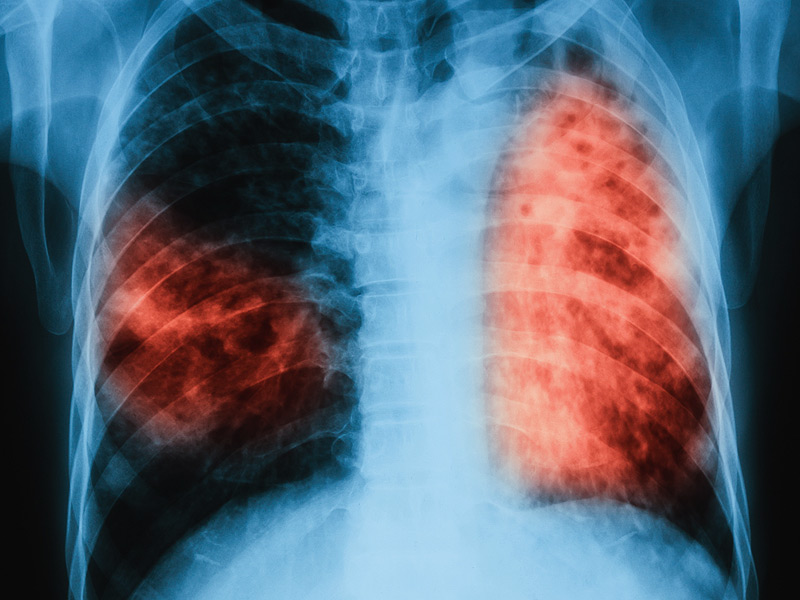

Khuẩn lao - căn bệnh làm 1,8 triệu người chết mỗi năm

Tất nhiên, nói cách thức nào đi nữa thì lao phổi cũng là một trong những căn bệnh nguy nan nhất trên thế giới. Ước tính chỉ trong năm 2015, đã có 1,8 triệu người chết vì căn bệnh này.

Kết quả, số lượng người đang nhiễm khuẩn lao rơi tham gia khoảng 1,7 tỉ người - nghĩa là gần 1/4 dân số nhân loại hiện nay. Về tỉ lệ thì có thể giảm sút, nhưng con số thực tiễn vẫn đang ở mức cao.

80% số này đến trong khoảng các nước nhà tại châu Á và châu Phi, và thường tập trung ở đội ngũ người già. Đáng để ý, gần 100 triệu con trẻ bây giờ cũng đang nhiễm TB - con số vượt cả tổng số người tại Đức.